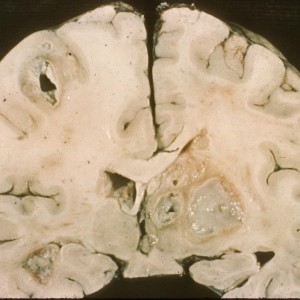

- Pathology with multinucleated giant cells and calcific vasculopathy (see below).